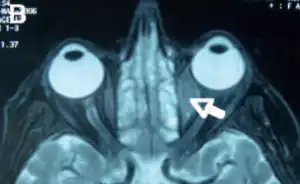

Orbital lymphoma

Orbital lymphoma is a common type of non-Hodgkin lymphoma that occurs near or on the eye. Common symptoms include decreased vision and uveitis. Orbital lymphoma can be diagnosed via a biopsy of the eye and is usually treated with radiotherapy or in combination with chemotherapy.